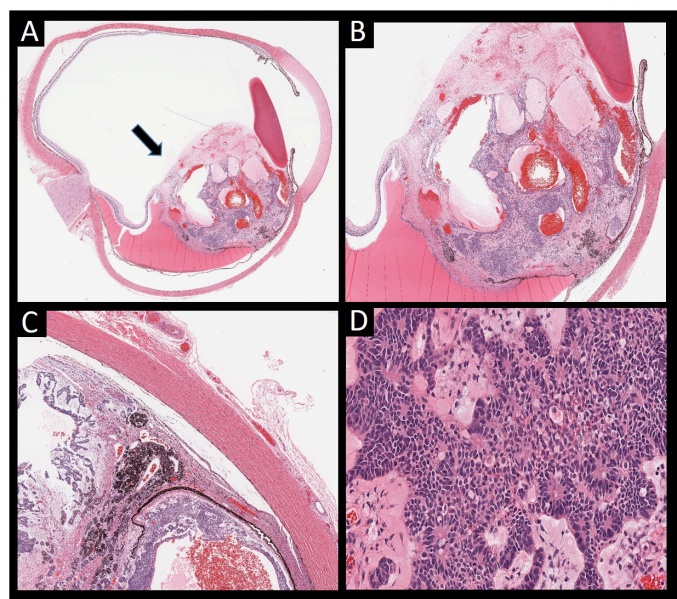

Figure 2 – Histopathological examination postenucleation of an eye with a tumor filling a large portion of the vitreous shows a: large tumor arising from the ciliary body (arrow) (A). The ciliary body mass shows basophilic cells forming ribbons and tubes with interspersed largely dilated vessels and cysts (B). Tumor cells appear to invade the choroid, with adjacent exudative retinal detachment (C). The tumor cells are round, small and deeply basophilic with some retinoblastoma differentiation. Multiple mitotic figures are present diagnostic of a malignant nonteratoid medulloepithelioma (D).